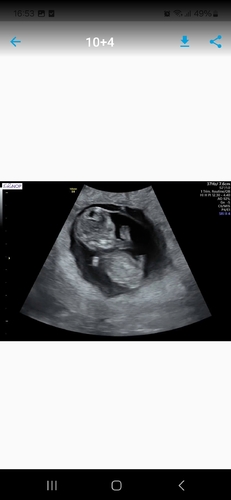

Ik ben nu 10+4 van baby nummer 2 en ik heb zometeen mijn termijn echo vind het altijd weer zo spannend 馃檲

10+4